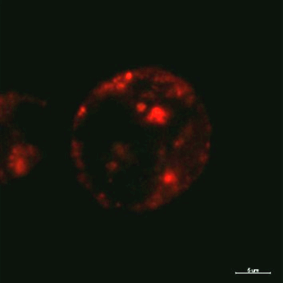

The technique of conjugation of antibody with ND is based on the reaction, which is both efficient and selective, namely, the reaction between activated carboxyl groups of nanodiamonds and aminogroups of antibodies, resulting in amide bond formation. Chlorine е6 was conjugated with nanodiamonds by the interaction of aminogroups on the basis of ND with activated carboxyl groups of chlorine е6, in the result of which amide bond is formed too. The synthesis of Chlе6-ND-АТ complex was conducted in three stages: 1) activation of nanodiamond carboxyl group by tionylchloride; 2) activation of chlorine е6 carboxyl group and its interaction with free amimogropus of ND; 3) connection of antibody to ND-Chl е6 complex to activated ND carboxyl groups. In order to confirm the interaction of the nanocomplex with living cells laser scanning microscopy of nanocomplex-containing suspension of green monkey kidney cells has been performed (Figure 1). Intracellular chlorine e6 distribution was registered based on its fluorescence under 488 nm excitation.

Figure 1 Confocal image of intracellular distribution of Ab-NВ-Chle6 complex in living green monkey kidney cells.